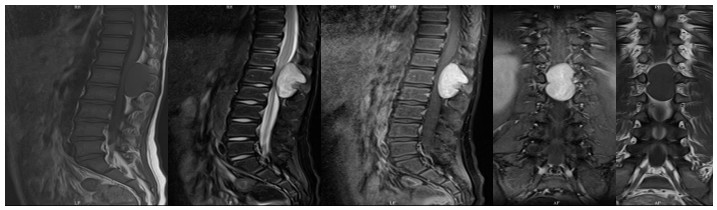

59歲鄒阿姨術(shù)前胸椎MRI檢查

原來端午節(jié)前一天,科室收治兩位急診患者。一個因急性腰背疼痛、行走困難1天入院的10歲小孩,一位因長期下肢麻木、脹痛不適數(shù)年,近2天突發(fā)下肢行走困難、感覺障礙的59歲患者鄒阿姨。在予以完善患者入院相關(guān)檢查后,醫(yī)師團(tuán)隊主要考慮胸椎椎管腫瘤、腰椎椎管腫瘤占位,目前患者出現(xiàn)下肢不全癱瘓癥狀,病情明顯加重,脊柱外科錢軍主任仔細(xì)檢查,反復(fù)研究患者的病例資料,判斷這兩位患者是因脊椎管內(nèi)腫瘤引起的神經(jīng)系統(tǒng)功能障礙。對于這兩位患者來說,切除腫瘤,解除壓迫,迫在眉睫。然而上胸椎椎管內(nèi)腫瘤是一種極為棘手的病變,椎管空間狹小,手術(shù)操作困難,脊髓被腫瘤壓迫嚴(yán)重,如稍有不慎,在手術(shù)過程中都有可能加重脊髓組織的損傷,造成患者癱瘓,因此胸椎管手術(shù)難度大、風(fēng)險高。椎管內(nèi)腫瘤切除一直是骨科領(lǐng)域富有挑戰(zhàn)性的難題。秉承“醫(yī)者仁心”的理念,提高患者生存質(zhì)量為目的,以治療此類疾病較為豐富的臨床經(jīng)驗為基礎(chǔ),脊柱外科團(tuán)隊克服困難、迎難而上,決定為患者進(jìn)行手術(shù)。